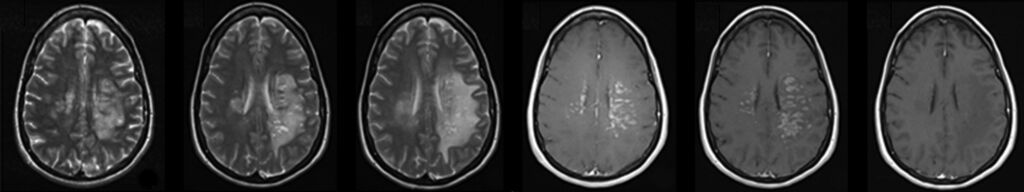

Leveraging crowdsourcing expertise backed by AI/ML developed internally and through partners to improve accuracy and expedite diagnosis.